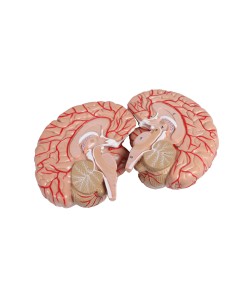

Dal cranio in 22 parti con incastri magnetici ai modelli di colonna vertebrale, da quelli di articolazioni a quelli di cuore, ogni pezzo della nostra collezione è progettato per un’immersione totale nello studio dell’anatomia umana. I nostri modelli, realizzati tramite scansioni di ossa vere, garantiscono un’esperienza tattile autentica e una fedeltà di peso quasi identica agli originali.